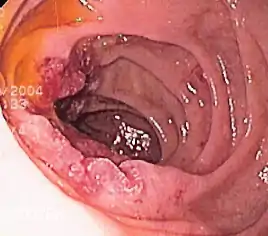

Cancers of the mouth, esophagus, pharynx, and larynx

Alcohol consumption at any quantity is a risk factor for cancers of the mouth, esophagus, pharynx and larynx. The U.S. National Cancer Institute states "Drinking alcohol increases the risk of cancers of the mouth, esophagus, pharynx, larynx, and liver in men and women, … In general, risks increases above baseline with any alcohol intake (mild; <2 glass of wine per week) and increases significantly with moderate alcohol intake (one glass of wine per day) with highest risk in those with greater than 7 glasses of wine per week. (A drink is defined as 12 ounces of regular beer, 5 ounces of wine, or 1.5 ounces of 80-proof liquor.) … Also, using alcohol with tobacco is riskier than using either one alone, because it further increases the chances of getting cancers of the mouth, throat, and esophagus."[41] The federal government's Dietary Guidelines for Americans 2010 defines moderate alcohol drinking as up to one drink per day for women and up to two drinks per day for men. Heavy alcohol drinking is defined as having more than three drinks on any day or more than seven drinks per week for women and more than four drinks on any day or more than 14 drinks per week for men.

The International Head and Neck Cancer Epidemiology (INHANCE) Consortium co-ordinated a meta-study on the issue.[42] A study looking at laryngeal cancer and beverage type concluded, "This study thus indicates that in the Italian population characterized by frequent wine consumption, wine is the beverage most strongly related to the risk of laryngeal cancer."[43]

A review of the epidemiological literature published from 1966 to 2006 concluded that:

- The risk of esophageal cancer nearly doubled in the first two years following alcohol cessation, a sharp increase that may be due to the fact that some people only stop drinking when they are already experiencing disease symptoms. However, risk then decreased rapidly and significantly after longer periods of abstention.

- Risk of head and neck cancer only reduced significantly after 10 years of cessation.

- After more than 20 years of alcohol cessation, the risks for both cancers were similar to those seen in people who never drank alcohol.[44][45]

A study concluded that for every additional drink regularly consumed per day, the incidence of oral cavity and pharynx cancers increases by 1 per 1000. The incidence of cancers of the esophagus and larynx increase by 0.7 per 1000.[40]

A 2008 study suggests that acetaldehyde (a breakdown product of alcohol) is implicated in oral cancer.[46][47]